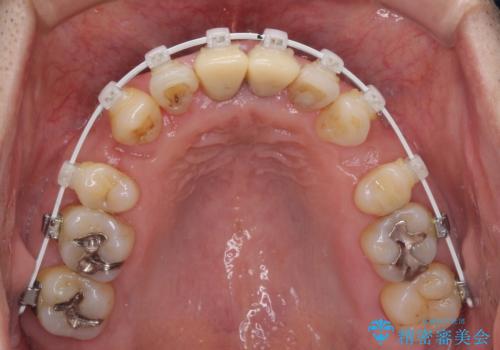

八重歯と突出感を改善 ワイヤー装置での矯正治療

- 八重歯を気にして来院された患者様です。

上顎前歯の突出感と右上の八重歯を気にされていたので、上顎左右の第一小臼歯2本を抜歯し、ワイヤー装置にて矯正治療を行うこととしました。

上顎前歯に装着されていた保険診療の前歯は見た目が気になるとのことであったので、矯正治療後にオールセラミッククラウンにて補綴治療を行うこととしました。